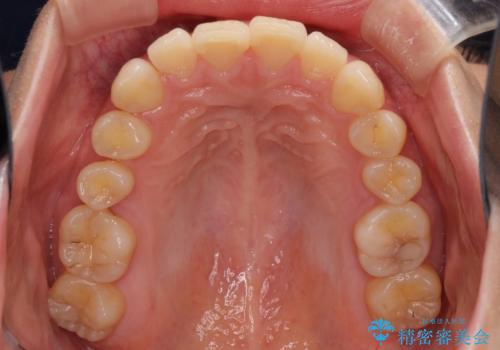

上顎前突 目立たないワイヤー装置での抜歯矯正

- 口元の突出感改善を希望して来院された患者様です。

口元を積極的に引っ込めるために、上下左右の小臼歯計4本を抜歯することとしました。

左右ともに下顎に対して上顎歯列が前方位にある上顎前突であったので、上顎歯列全体を後方に移動させることで上下咬み合わせを改善し、その上で抜歯矯正により口元の突出感を改善させていきました。